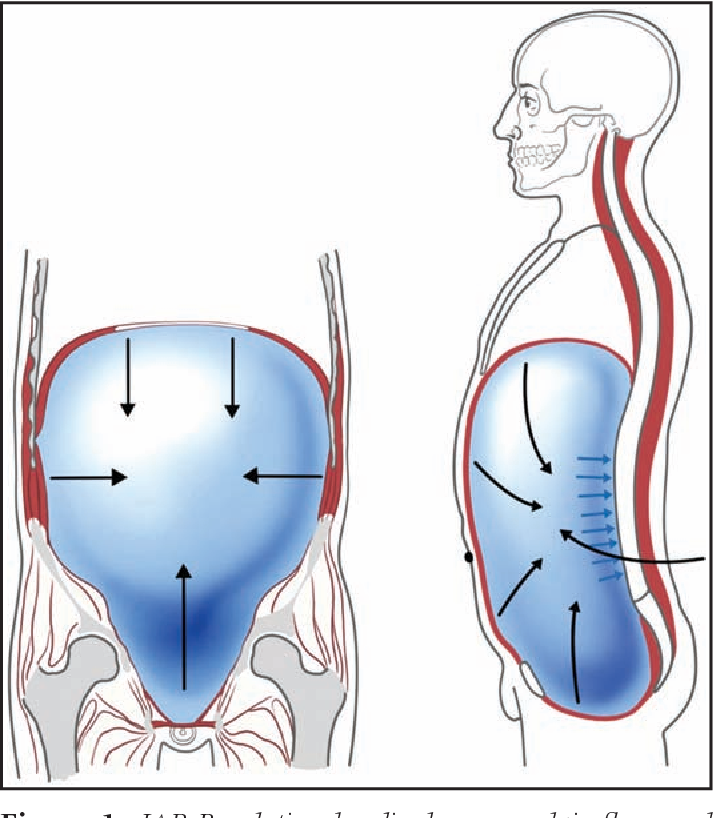

Rola ciśnienia śródbrzusznego w terapii DNS

Ciśnienie śródbrzuszne odgrywa istotną rolę w stabilizacji kręgosłupa w terapii (DNS). Optymalna stabilizacja kręgosłupa zależy od harmonijnej współpracy i koordynacji między przeponą, mięśniami dna miednicy oraz mięśniami brzucha, które regulują odpowiednie ciśnienie śródbrzuszne.

Ciśnienie śród brzuszne ma kluczowe znaczenie dla stabilizacji kręgosłupa w płaszczyźnie strzałkowej, redukując siły kompresyjne oddziałujące na kręgosłup. Współpracuje ono także z mięśniami prostownikami kręgosłupa, zapewniając odpowiednie napięcie, oraz stabilizuje kręgosłup lędźwiowy od strony grzbietowej.

Stabilizacja kręgosłupa silnie koreluje z wzorcem oddechowym, funkcją przepony oraz mięśniami dna miednicy. Ogólna koordynacja i aktywacja mięśni głębokich tułowia odgrywają zasadniczą rolę w zapewnieniu stabilizacji kręgosłupa w terapii DNS.

Pojedyncza aktywacja mięśni tułowia lub jednego komponentu składającego się na stabilizację tułowia nie byłaby wystarczająca, aby dynamicznie wytwarzać odpowiednie ciśnienie śródbrzuszne w odpowiedzi na wymagania posturalne dostosowane do zmiany ruchu. Osłabiona stabilizacja kręgosłupa i słaba funkcja posturalna mięśni dna miednicy i przepony mogą prowadzić do dolegliwości bólowych w dolnym odcinku lędźwiowym kręgosłupa.

Podejście terapeutyczne DNS podkreśla, jak ważne jest dokładne synchronizowanie mięśniowe oraz koordynacja dla prawidłowego ruchu oraz przeciwstawiania się siłom kompresyjnym, które oddziałują w trakcie ruchu.